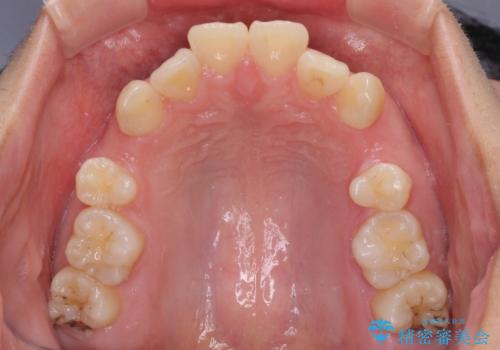

- 口元の閉じにくさを気にして来院された患者様です。

地元で矯正治療を始める予定で上顎左右第1小臼歯2本を抜歯したものの、その後転居したため治療が滞っているとのことでした。

上下ともに歯列が前方に突出していたため、上下左右の第一小臼歯4本を抜去する方針(既に上顎は抜歯されています)で、ワイヤー装置による矯正治療を行うこととしました。